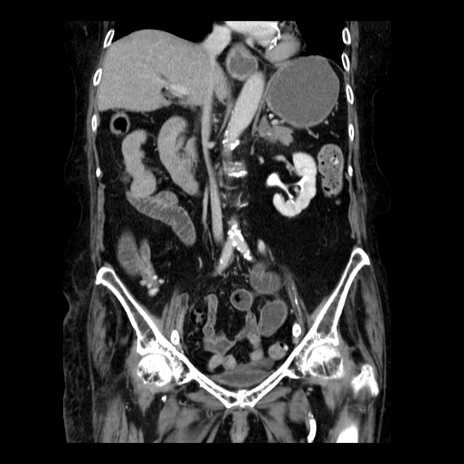

症例14(冠状断像)

【症例】 90歳代女性

【主訴】 腹痛・嘔吐

【現病歴】今朝から左側腹部痛を認めた。 経過観察していたが、嘔吐を認めたため来院。

【既往歴】 子宮癌術後

【身体所見】 意識清明、BP 127/54mmHg、P 98bpm Sp02 95%(RA)、BT 35.8°C、腹部平坦・軟腸ぜん動音聴取良好、右下腹部圧痛(+) 反跳痛なし

【データ】WBC 9800、CRP 0.46